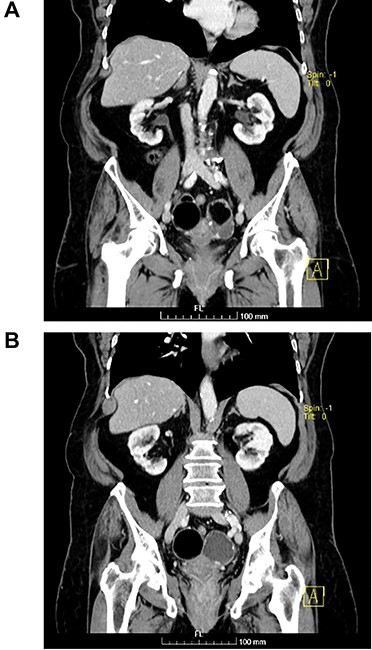

(A and B) Axial images of CT scan showing in the right ovary, a solid mass with predominantly fat density of 55 mm; and in the left ovary, a predominantly cystic mass of 65 mm.

The authors report the case of an asymptomatic 76-year-old female patient, referred to our Gynaecologic Clinic, due to suspicious adnexal lesions on a pelvic ultrasound (US). Menopause occurred at age 53. She had no history of abnormal uterine haemorrhage. Her menstrual cycles had been regular. She had had three gestations: two late abortions and one normal delivery, after which she breastfed. At our clinic, upon examination, vulva, vagina and cervix had no apparent lesions. The vaginal US revealed a right adnexal avascular cystic lesion of 65 mm, a left adnexal hyperechogenic cystic lesion of 60 mm, a normal sized uterus, a diffusely heterogeneous myometrium, an endometrial thickness of 8 mm and heterogenous intracavitary liquid. Her risk of ovarian malignancy assessment (ROMA) score was 28.1%, for a cut-off of 25.3%. Cancer antigen (CA) 125 and Human epididymis protein 4 (HE4) were 25.9 and 98.2, respectively. Lactate dehydrogenase (LDH), alpha fetoprotein (AFP) and beta human chorionic gonadotropin (bHCG) were normal. She subsequently had a magnetic resonance (MR) done (Fig. 1), which suggested bilateral ovarian teratoma. She also had an upper digestive endoscopy and a hysteroscopy that were normal and a computed tomography (CT) done (Figs 2–4) that showed: in the right adnexal region, a solid well-demarcated tumoural mass of 55 mm, with predominantly fat density, peripherical calcifications and a central hyperdense image (similar to a tooth), suggestive of a teratoma; in the left adnexal region, a predominantly cystic bilobated tumoural mass of 65 mm, with peripherical calcifications and an area of fat density, also suggestive of teratoma; and no additional disease. This case was presented at our Multidisciplinary Tumour Board, where surgery was proposed. Thus, she underwent exploratory laparotomy, peritoneal washing, total hysterectomy and bilateral adnexectomy, which ran uneventfully. Intra-operative frozen section excluded ovarian malignancy. She had an uneventful recovery and was discharged home on the third post-operative day. The pathological report revealed bilateral mature cystic teratoma with representation of the three germinative layers and thyroid parenchymal tissue (struma ovarii) (Fig. 5). Both ovaries were atrophic and had a cavitated lesion covered by respiratory epithelium with hyaline cartilaginous, adipose, smooth muscular and mucosa-associated lymphoid tissues (positivity for CD3 and CD20), seromucinous glands and thyroid follicles (homogenous positivity for thyroglobulin). Thyroid follicles were well differentiated, without features of malignancy. Fallopian tubes were normal. There were also uterine leiomyomas and a mucosal endocervical polyp. She was euthyroid and had a thyroid US done, which was normal. Follow-up at first post-operative month, remaining asymptomatic.